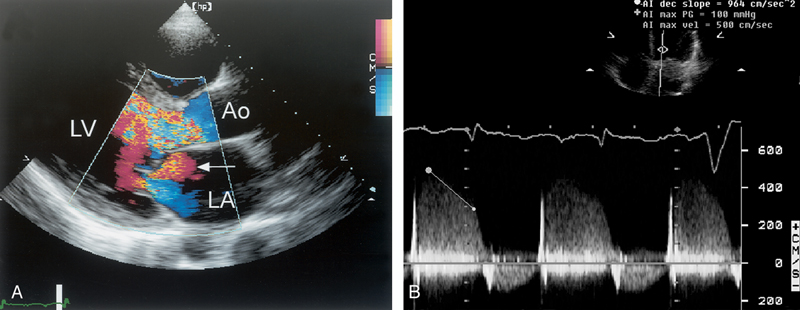

فحوصات تشخيصية لبعض امراض القلب والشرايين التاجية